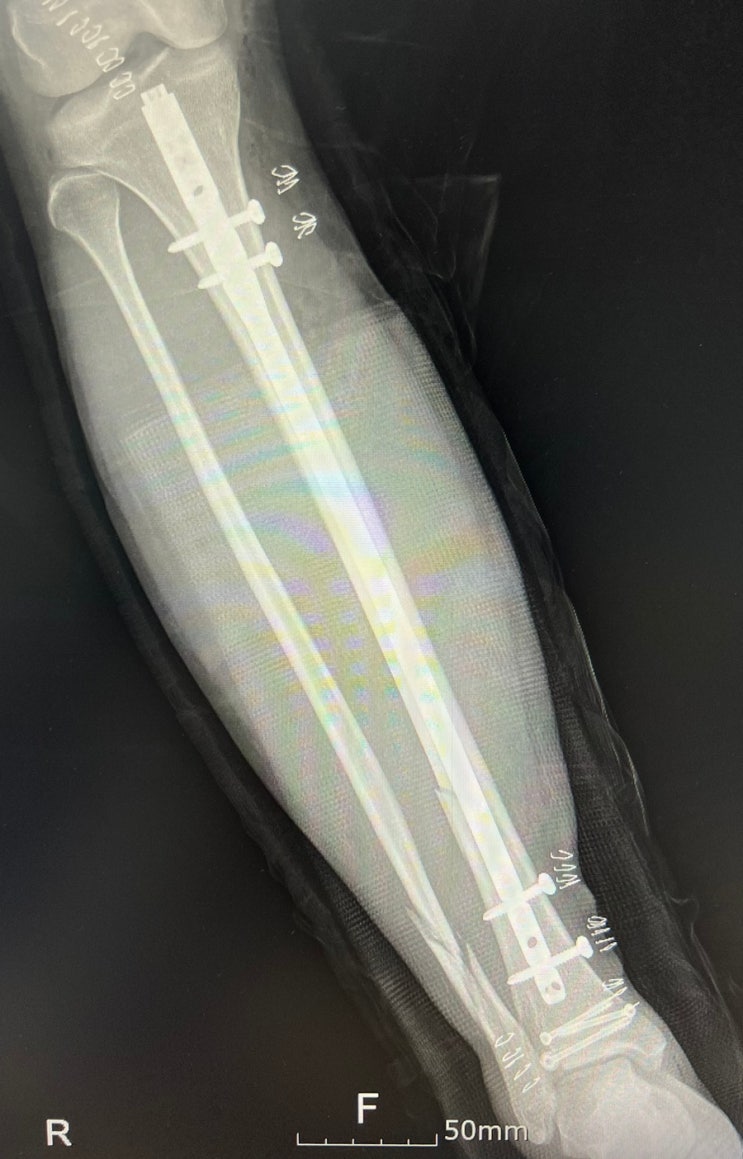

[골절일기 #15] 수술흉터, 외출! 골절 4-6주차 / 경비골 골절, 골수강내금속정

[골절일기 #07] 수술 당일 / 경비골 골절, 골수강내금속정

[골절일기 #05] 수술! / 경비골 골절, 골수강내금속정